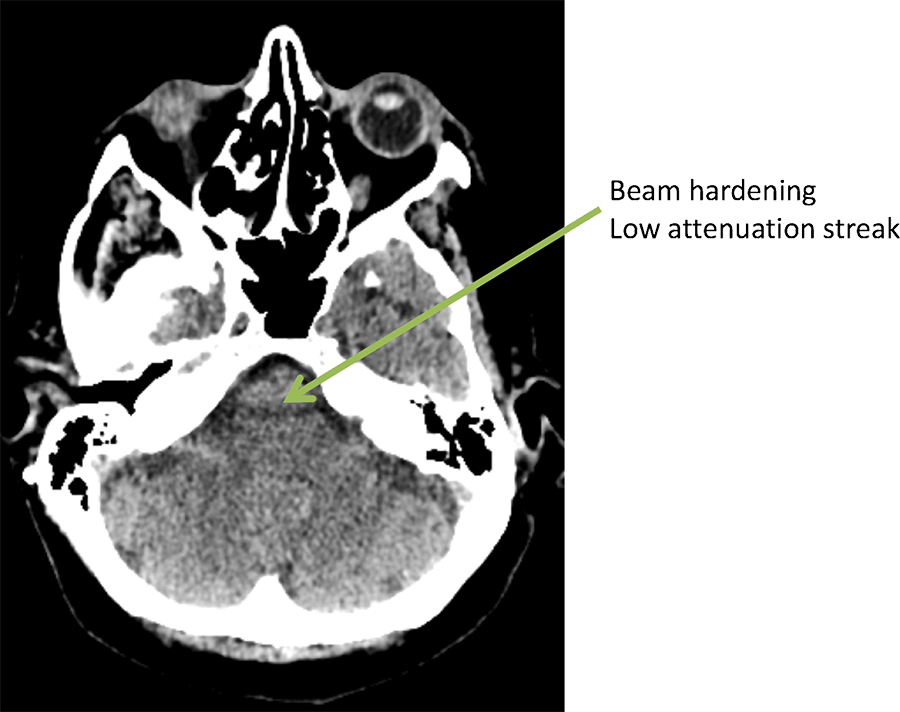

Ct Tube Arcing Artifact . Artifact on two to three consecutive slices of the ct transaxial images of a patient, which showed near‑parallel streaks across the transaxial. Ct artifacts are common and can occur for various reasons. One or more concentric rings in image. Knowledge of these artifacts is important because they can mimic. Ct 37 artifact from tube arcing (frame from animation in presentation)

Ct 37 artifact from tube arcing (frame from animation in presentation) Artifact on two to three consecutive slices of the ct transaxial images of a patient, which showed near‑parallel streaks across the transaxial. Ct artifacts are common and can occur for various reasons. One or more concentric rings in image. Knowledge of these artifacts is important because they can mimic.

Ct Tube Arcing Artifact Ct artifacts are common and can occur for various reasons. Ct 37 artifact from tube arcing (frame from animation in presentation) One or more concentric rings in image. Ct artifacts are common and can occur for various reasons. Knowledge of these artifacts is important because they can mimic. Artifact on two to three consecutive slices of the ct transaxial images of a patient, which showed near‑parallel streaks across the transaxial.